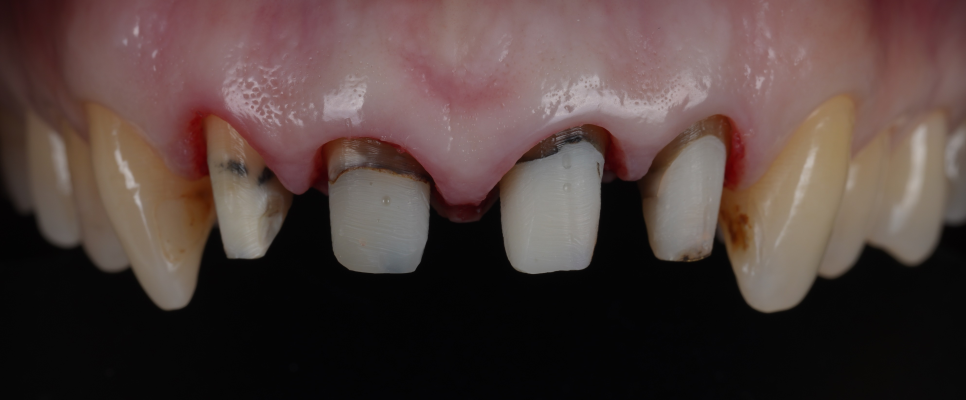

환자분의 앞니는 PFM이라는 재료로 씌워져 있었는데요.

PFM은 Pocelain Fused Metal의 약자로, 메탈 위에 포세린(흰색 도자기)을 얹어서 제작한 보철이에요.

보시는 것처럼, 가장 안에 위치한 메탈이 시간이 지나면서 잇몸이 서서히 퇴축되며 경계부가 드러나 검게 보이게 돼요.

기존 보철 제거는 예상보다 까다로웠어요.

촬영 : 251022

금속이 두껍고 접착력이 강했는데요. 그럼에도 불구하고 치아 손상을 최소화하며 분리했죠.

이후 보철 제작을 위해 모양을 다듬고, 치관확장술로 잇몸 선을 정리하고 길이를 확보했어요.